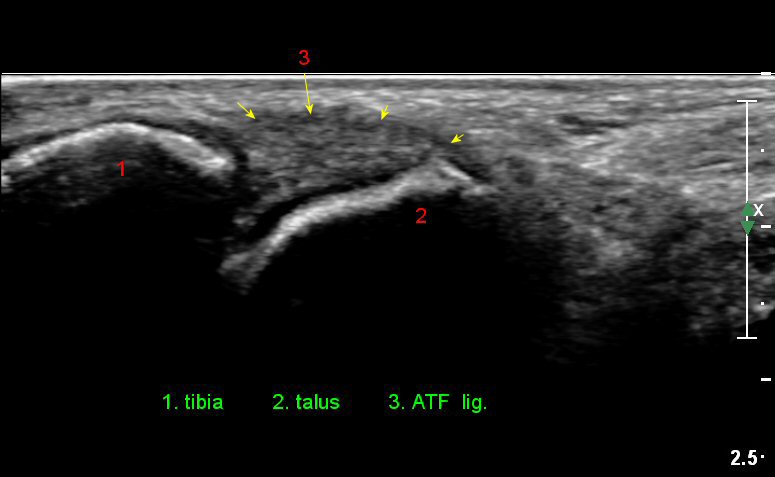

¹ß¸ñ°üÀý ¾ÕÂÊ Á¾´Ü¸é°Ë»ç¿¡¼­ ƯÀÌ ¼Ò°ßÀ» º¸ÀÌÁö ¾ÊÀ¸³ª(»çÁø 1)

ŽÃËÀÚ¸¦ ÀÎÁ¢ÇÑ ºÎÀ§·Î À̵¿ÇÏ´Ï ¼Ò·®ÀÇ °üÀý³» ¼ö¾×Àú·ù°¡ °üÂûµÈ´Ù(»çÁö 2).